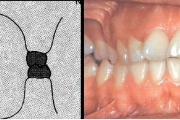

kahepoolse lõhega lapse hambumus

Valehambumus

Hammaste asendianomaaliad on tingitud tavaliselt arenguhäirest.